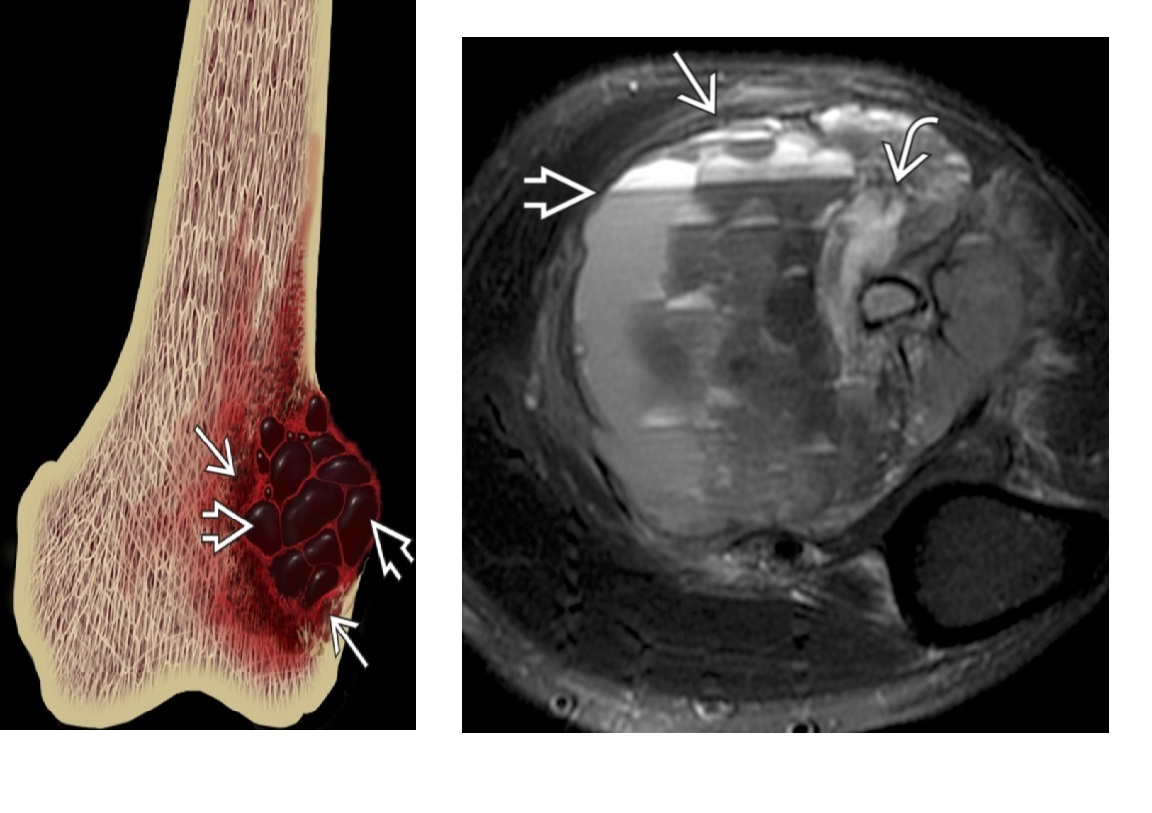

telangiectatic oestosarcoma

Distal Femur

Haemorrhagic and necrotic components

Fluid-fluid levels

Thus, heterogenous on T1 and T2

*Purely lytic but with aggressive features, less likely osteoid matrix

Solid components enhance

DDx

ABC

—Expansile lytic lesion arising in metaphysis

—No tumour nodularity and enhancement

- Thin peripheral and septal enhancement

GCT

—Mildly expansile metaphyseal lesion with extension to joint line

—Can be very aggressive and have soft tissue extension